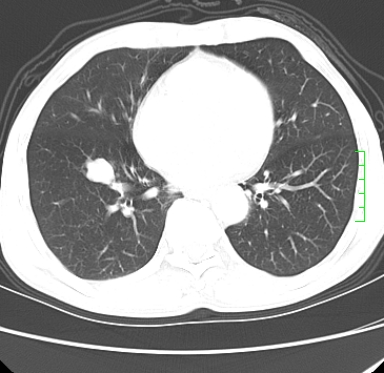

m,73y。膝关节疼痛伴双下肢水肿。入院常规胸片发现结节灶。增强为静脉期。

浅分叶、棘突,考虑右下肺周围型肺癌

考虑周围型肺癌  ,双上肺结核。

肿块周围可见局限性气肿,考虑肺癌可能性大。双肺上叶继发型肺结核。

指套征,强化明显,近侧肺组织局限性肺气肿,考虑支气管类癌,慢支、肺气肿、双上陈旧性tb、冠脉钙化。

鉴别:先天性支气管闭锁,变态反应性支气管肺曲霉菌病,肺癌,支气管囊肿,支扩黏液嵌塞。

1)考虑右肺下叶周围型肺癌。2)右肺上叶及左肺感染性病变(结核可能)。3)肺气肿。4)冠状动脉钙化。